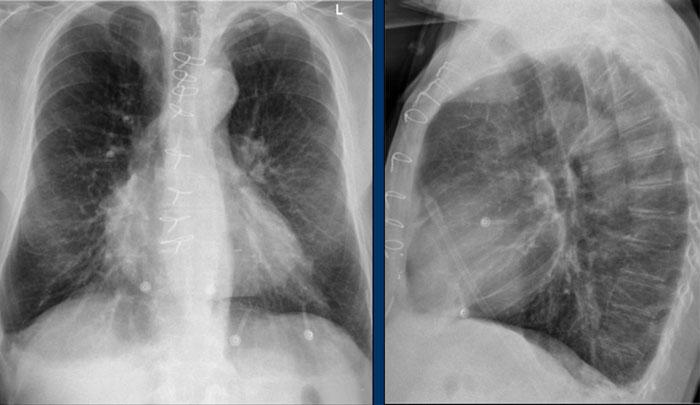

Giãn Nhĩ Trái

- Bệnh nhân có tiền sử bệnh van hai lá mạn tính và thay van tim.

- Giãn nhĩ trái mức độ nặng dẫn đến phồng cả bờ tim phải phía trên (mũi tên đen) và bờ tim sau trên tư thế nghiêng (mũi tên xanh dương).

Giãn Thất Phải

Hãy phân tích phim X-quang ngực tư thế thẳng và nghiêng trước, sau đó tiếp tục đọc.

Hình ảnh

- X-quang ngực cho thấy tim to mức độ nặng, chủ yếu do giãn thất phải (mũi tên vàng trên tư thế nghiêng).

- Cung động mạch chủ nhỏ (mũi tên xanh dương), kèm giãn thân động mạch phổi và động mạch phổi phải thùy dưới.

- Các dấu hiệu này gợi ý luồng thông trái-phải với tăng áp động mạch phổi thứ phát.